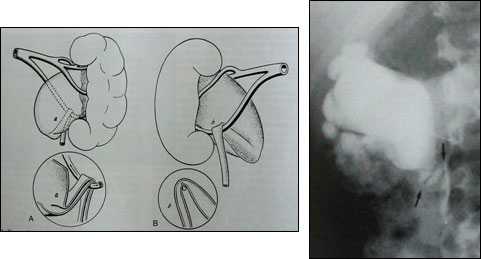

А. Сужение мочеточника за счет уменьшения внутреннего просвета ( Intrinsic) (сегментарная дисплазия,вр.стеноз) (Рис.1).

Б. Сдавление просвета мочеточника снаружи (Extrinsic) пересекающим сосудом, добавочным или нижнеполярным сосудом почки (Рис.2), опухолью, инфильтратом (воспалительный процесс в забрюшинном пространстве)

Рис.1 Сужение мочеточника за счет уменьшения внутреннего просвета (Intrinsic)

Рис.2. Сдавление мочеточника абберантным (отклоненным) сосудом

1. При лечении гидронефроза операцией выбора (золотой стандарт) остается пластика прилоханочного отдела мочеточника по Хайнсу-Андерсену (Рис.6).

Рис.6 Операция Хайнса-Андерсена.

А. Определение зоны стеноза мочеточника. Б. Иссечение стеноза, резекция лоханки, рассечение мочеточника вдоль.В. Формирование лоханочномочеточникового анастомоза.